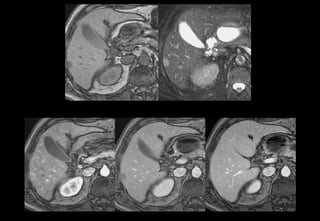

Hopital CROIX ROUSSE

Xóa nền

T1

GADO

T2